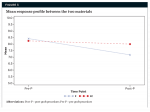

Buccolingual-ridge dimensions were also compared. Mean response profile between the two study materials showed that the SECG was dimensionally more stable than the ABBM. The change patterns from pre- and post-procedures between the two materials did not differ significantly (Figure 3).